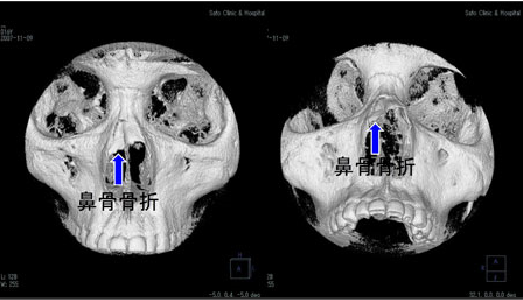

鼻骨骨折びこつこっせつとは

鼻骨骨折とは、鼻の上半分を構成する鼻骨に生じる骨折のことを指します。鼻骨は薄い骨であり、顔面に対しての外力をきっかけとして骨折が生じやすく、比較的頻度の高い骨折です。肘が当たるなどの軽微な外力で生じることが多いですが、時に、より大きな外力が加わることによって鼻骨以外の部位にも同時に骨折が生じることもあります。

鼻骨骨折が生じると、骨折が生じた部位に痛みが生じます。局所を押さえると痛みは増強し、鼻血も同時に見られます。骨折によって鼻骨の形が変形してしまい、外から見た際に鼻が歪んで見えることもあります。

鼻骨の変形に関連して、空気の通り道としての鼻の穴の大きさに著しい左右差が生じてしまい、鼻が詰まったような感覚や、息苦しさを覚えることもあります。また、骨折を生じた部位周辺に出血斑やむくみが生じることもあります。